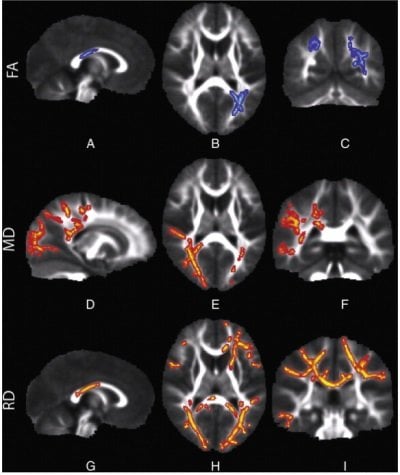

of children with sensory processing disorders. Row FA: The blue areas show

white matter where water diffusion was less directional than in typical children,

ndicating impaired white matter microstructure. Row MD: The red areas show white matter where the overall rate of water diffusion was higher than in typical

children, also indicating abnormal white matter. Row RD: The red areas show

white matter where SPD children have higher rates of water diffusion perpendicular to the axonal fibers, indicating a loss of integrity of the fiber bundles comprising the white matter tracts. Credited to UCSF.

In the study, researchers used an advanced form of MRI called diffusion tensor imaging (DTI), which measures the microscopic movement of water molecules within the brain in order to give information about the brain’s white matter tracts. DTI shows the direction of the white matter fibers and the integrity of the white matter. The brain’s white matter is essential for perceiving, thinking and learning.

The imaging detected abnormal white matter tracts in the SPD subjects, primarily involving areas in the back of the brain, that serve as connections for the auditory, visual and somatosensory (tactile) systems involved in sensory processing, including their connections between the left and right halves of the brain.

“These are tracts that are emblematic of someone with problems with sensory processing,” said Mukherjee. “More frontal anterior white matter tracts are typically involved in children with only ADHD or autistic spectrum disorders. The abnormalities we found are focused in a different region of the brain, indicating SPD may be neuroanatomically distinct.”

The researchers found a strong correlation between the micro-structural abnormalities in the white matter of the posterior cerebral tracts focused on sensory processing and the auditory, multisensory and inattention scores reported by parents in the Sensory Profile. The strongest correlation was for auditory processing, with other correlations observed for multi-sensory integration, vision, tactile and inattention.

The abnormal microstructure of sensory white matter tracts shown by DTI in kids with SPD likely alters the timing of sensory transmission so that processing of sensory stimuli and integrating information across multiple senses becomes difficult or impossible.